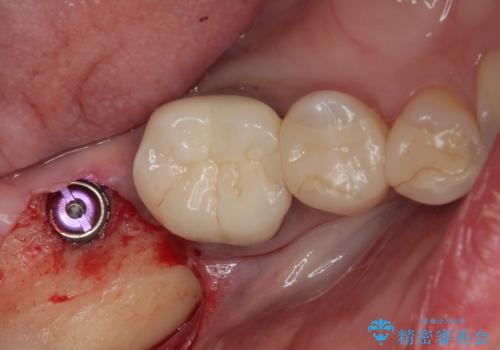

放置した奥歯 部分矯正を併用したインプラント補綴治療

- 右下欠損部のインプラント治療を希望して来院された患者様です。

右下の欠損部を長期間欠損を放置していたことで、咬み合う上の奥歯が動いてしまっていたので、まずは上顎奥歯の部分矯正を行うこととしました。

理想的な咬み合わせに改善した上で、インプラント補綴治療を行うこととしました。